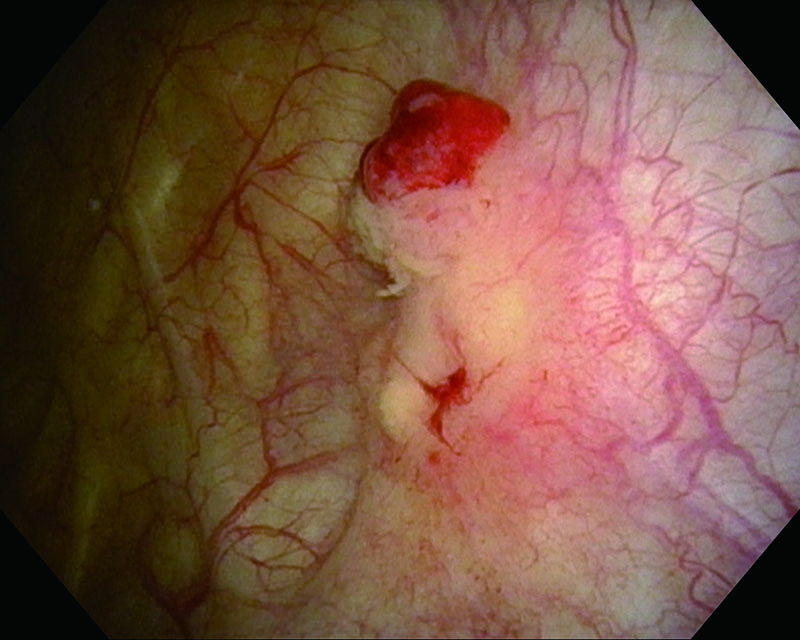

Rubor mucosa, 81 años, hombre

Luz blanca

NBI

Histología UC, CIS

Comentarios

El caso sospechaba carcinoma in situ e identificaba un rubor en la mucosa de la vejiga. El examen histopatológico reveló CIS.